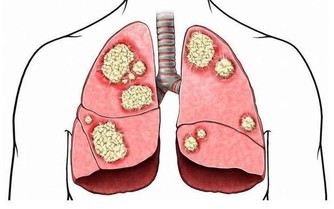

膝蓋關節一直是諸多長輩的困擾,尤其到了中老年又缺乏運動的情況下,

很容易伴隨著天氣或者其他原因而不適...